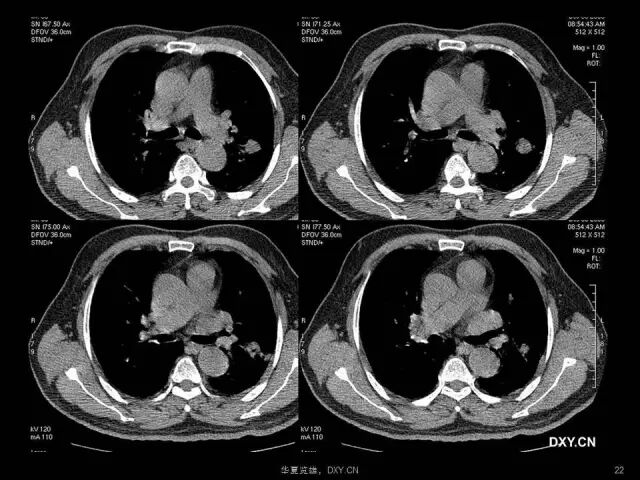

肺炎、肺癌、肺结核在影像学上的征象往往千变万化。